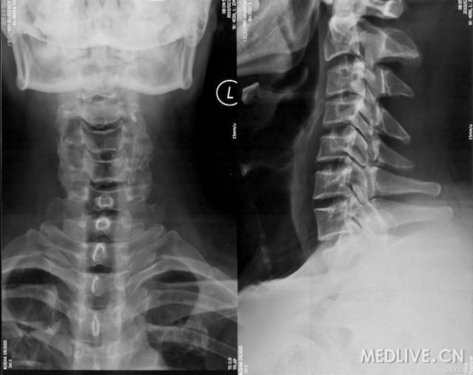

颈椎CT

CT:未见后纵韧带骨化。